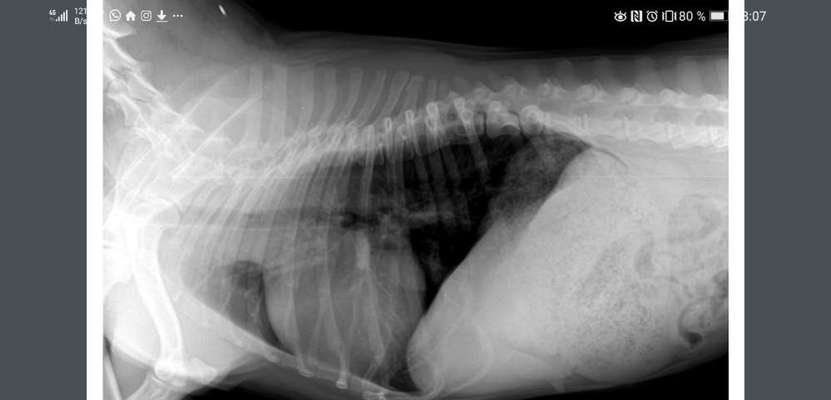

Ganz lieben Dank 💐 ich versuche das umzusetzen.... Auf Futter und Gewicht achte ich schon sehr..... Das Röntgenbild ist auch schon gelaufen.... Sieht nicht gut aus der BWS betreffend.